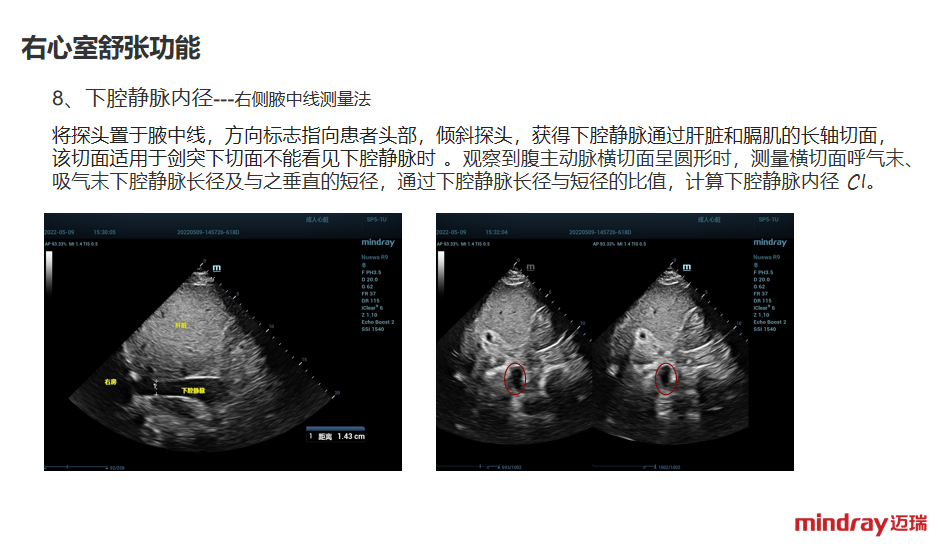

下腔静脉的超声,测量参数正常值及解读,剑突下、腋中线测量方法

下腔静脉的测量,评估容量的方法和参考指标